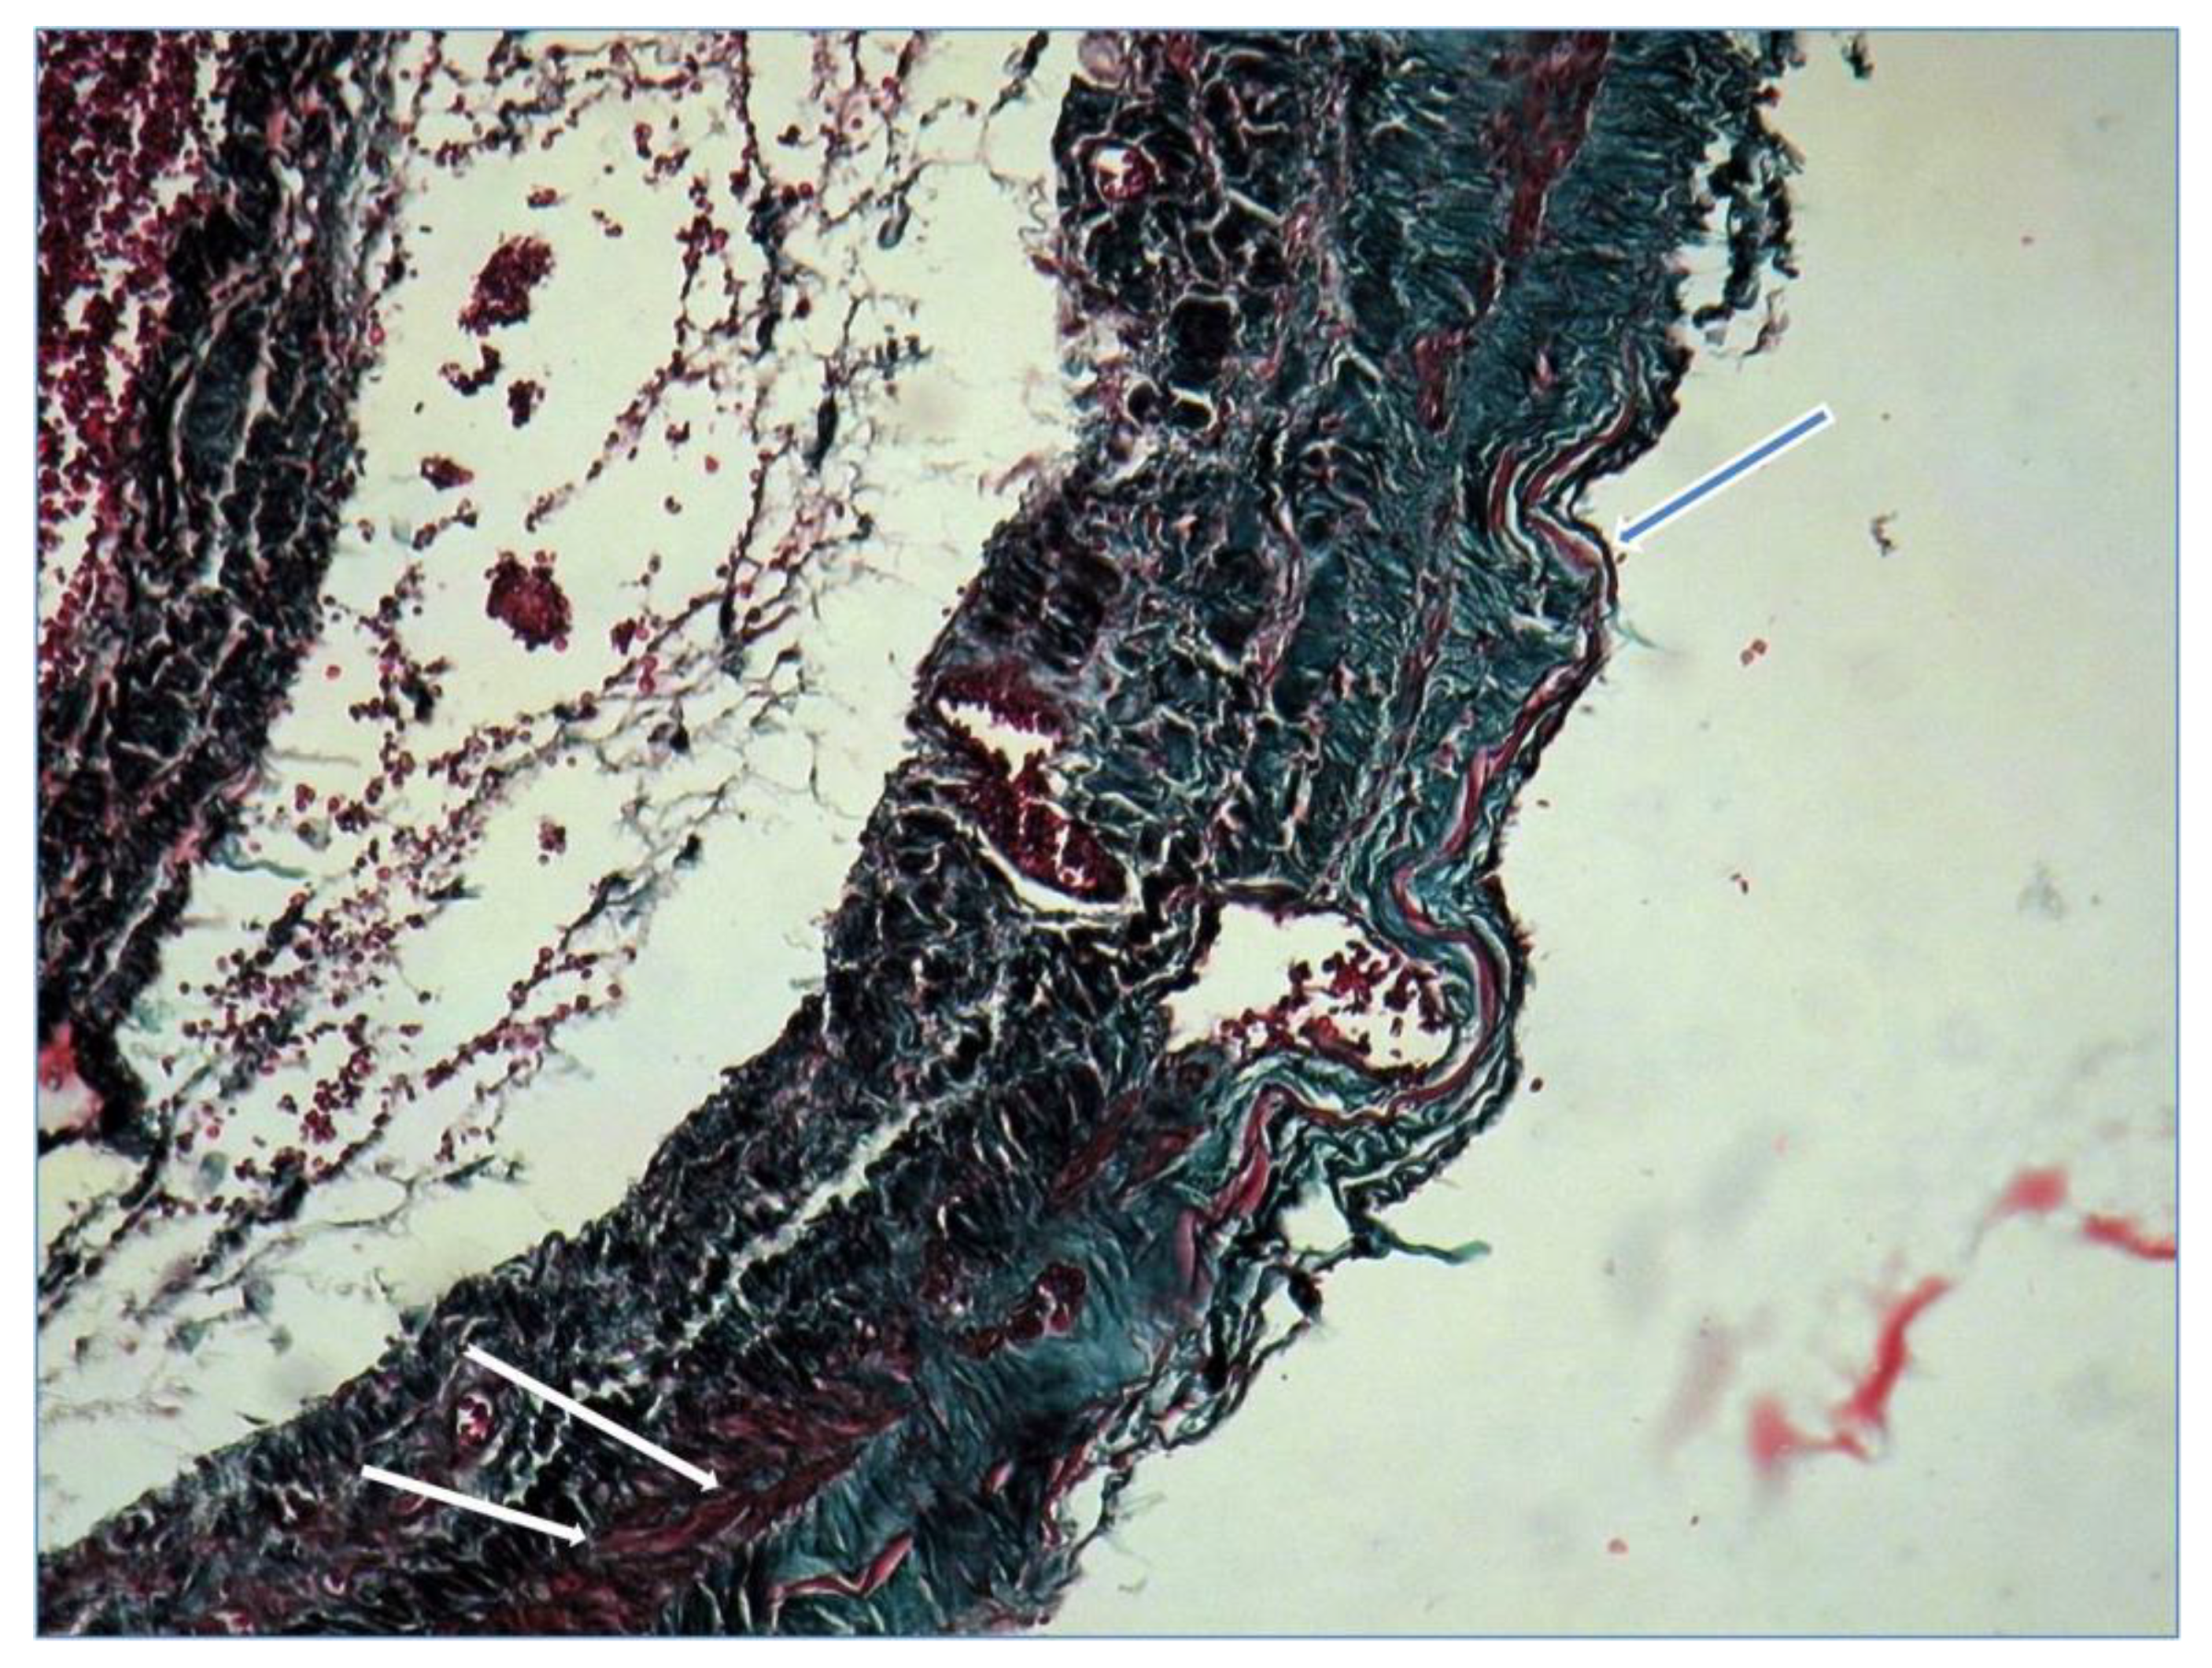

Microscopic examination with tricrom masson staining protocol showed continuous thinned venous layer with fragmentation of elastin fibres (blue arrow) and few smooth muscle fibers (white arrow) confirming the diagnosis of popliteal venous aneurysm (Figure 5).

Figure 5.

Microscopy confirming the diagnosis of popliteal venous aneurysm.